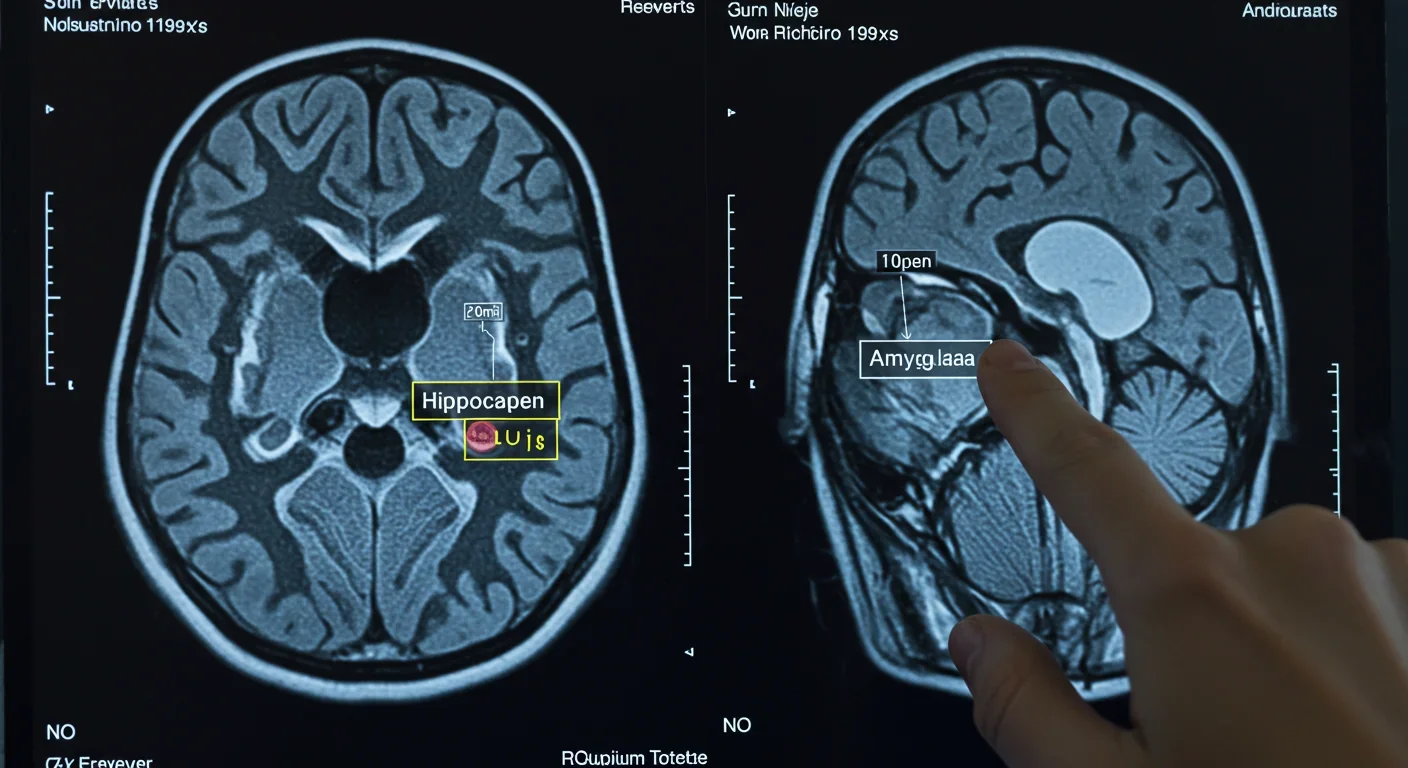

Researchers at Mount Sinai broke new ground by recording neural activity directly from deep within the brain during meditation. Using invasive electrodes implanted in eight epilepsy patients, they captured real-time changes in the amygdala and hippocampus - regions governing emotion and memory - during a 10-minute loving-kindness meditation session. Even first-time meditators showed immediate shifts in beta and gamma brain waves, electrical signatures known to be disrupted in depression and anxiety.

But acute changes are just the beginning. Structural brain imaging reveals that consistent practice over eight weeks produces measurable increases in gray matter density in key regions: the hippocampus (memory formation), the anterior cingulate cortex (attention and emotional regulation), and the insula (interoceptive awareness and empathy). Meanwhile, gray matter volume in the amygdala - your brain's alarm system - actually decreases, suggesting reduced reactivity to stress.

During loving-kindness meditation, you're essentially running neural drills. Each time you generate feelings of warmth toward yourself or others, you activate the anterior cingulate cortex (regulating attention and emotion), the insula (processing empathy and bodily states), and the prefrontal cortex (executive control). Do this daily for weeks, and those regions develop increased gray matter density - more neurons, more synaptic connections, more processing capacity.

The amygdala tells the opposite story. This almond-shaped structure triggers fear and stress responses. Meditation appears to reduce its gray matter volume, essentially down-regulating threat reactivity. Less reactive amygdala means lower stress hormones, including cortisol, which itself drives inflammatory processes.

The hippocampus benefits too. Critical for memory formation and emotional context, hippocampal volume increases with meditation practice, potentially explaining improved emotional regulation. You're literally building more capacity to contextualize experiences rather than react reflexively.